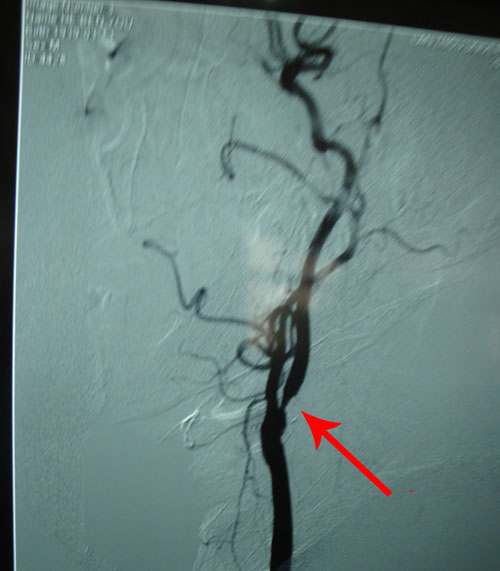

颈动脉DSA示:右侧颈动脉狭窄。

颈动脉超声:双侧颈动脉内膜增厚并斑块形成;左侧颈内动脉闭塞;右侧颈内动脉狭窄(70%-99%);左侧颈总动脉狭窄(50%-69%);右侧颈外动脉狭窄(<50%)

右侧颈内动脉可看到细微现状血流

该患者病例特点:老年男性,2月前行因大面积脑梗塞行左侧颞浅动脉—大脑中动脉吻合术后血流通畅,继发脑出血。此次复查颈动脉超声提示右侧颈内动脉狭窄(70%-99%);左侧颈总动脉狭窄(50%-69%)。为彻底治疗颈动脉狭窄病变,行颈动脉内膜剥脱术。

2010年9月25日,协作组张勤奕教授应邀前往兰州大学医学院第二附属医院为该患者顺利实施了左侧颈内动脉内膜剥脱术。